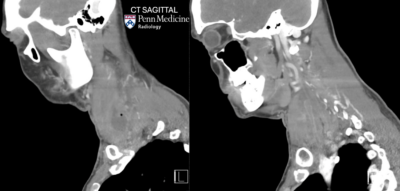

CT: There is a large intramuscular abscess within the inferior right sternocleidomastoid muscle with overlying cellulitis within the right anterolateral neck and reactive cervical lymphadenopathy. The airway is patent. There is associated thrombophlebitis of the right internal jugular vein, concerning for Lemierre syndrome.

Diagnosis: Lemierre syndrome